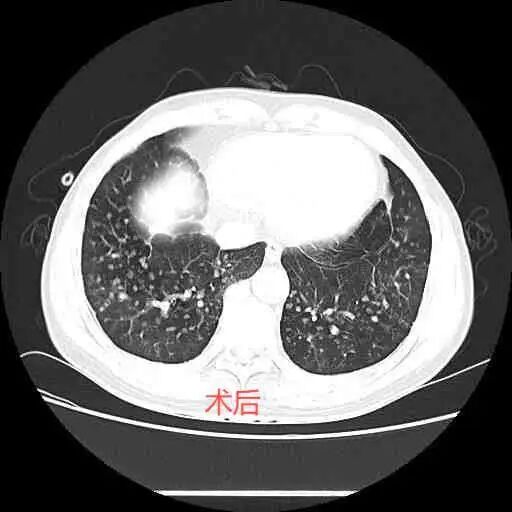

治療后,患者術(shù)后第一天,水封瓶氣泡明顯減少,第二天水封瓶未見水柱波動,第三天復(fù)查胸部CT提示氣胸明顯吸收,右肺復(fù)張,隨后患者康復(fù)出院。